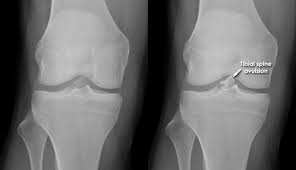

- Knee injuries

- Fractures